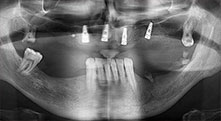

For what indications do you use the saws?

Bratu: We routinely use the instruments for harvesting bone blocks and splitting alveolar ridges. We also use the Piezomed B6/B7 for osteotomy of impacted teeth and removing failed implants. All indications that require deep, clean cuts.

Bratu: I consider piezo surgery a great leap forward in oral surgery. The technique makes bone preparation safer and easier. Little bone is lost, for example in extractions. This is very important in the aesthetic zone, particularly if immediate implantation is planned. Piezo surgery is also safer for soft tissue: injuries to membranes in the sinus are basically history, as are nerve injuries when bone blocks are being harvested. Data indicating reduced postoperative swelling and pain are also available. Piezo surgery is also ideal for preparation of sinus septa. And last but not least, our patients benefit from the atraumatic nature of this technology.